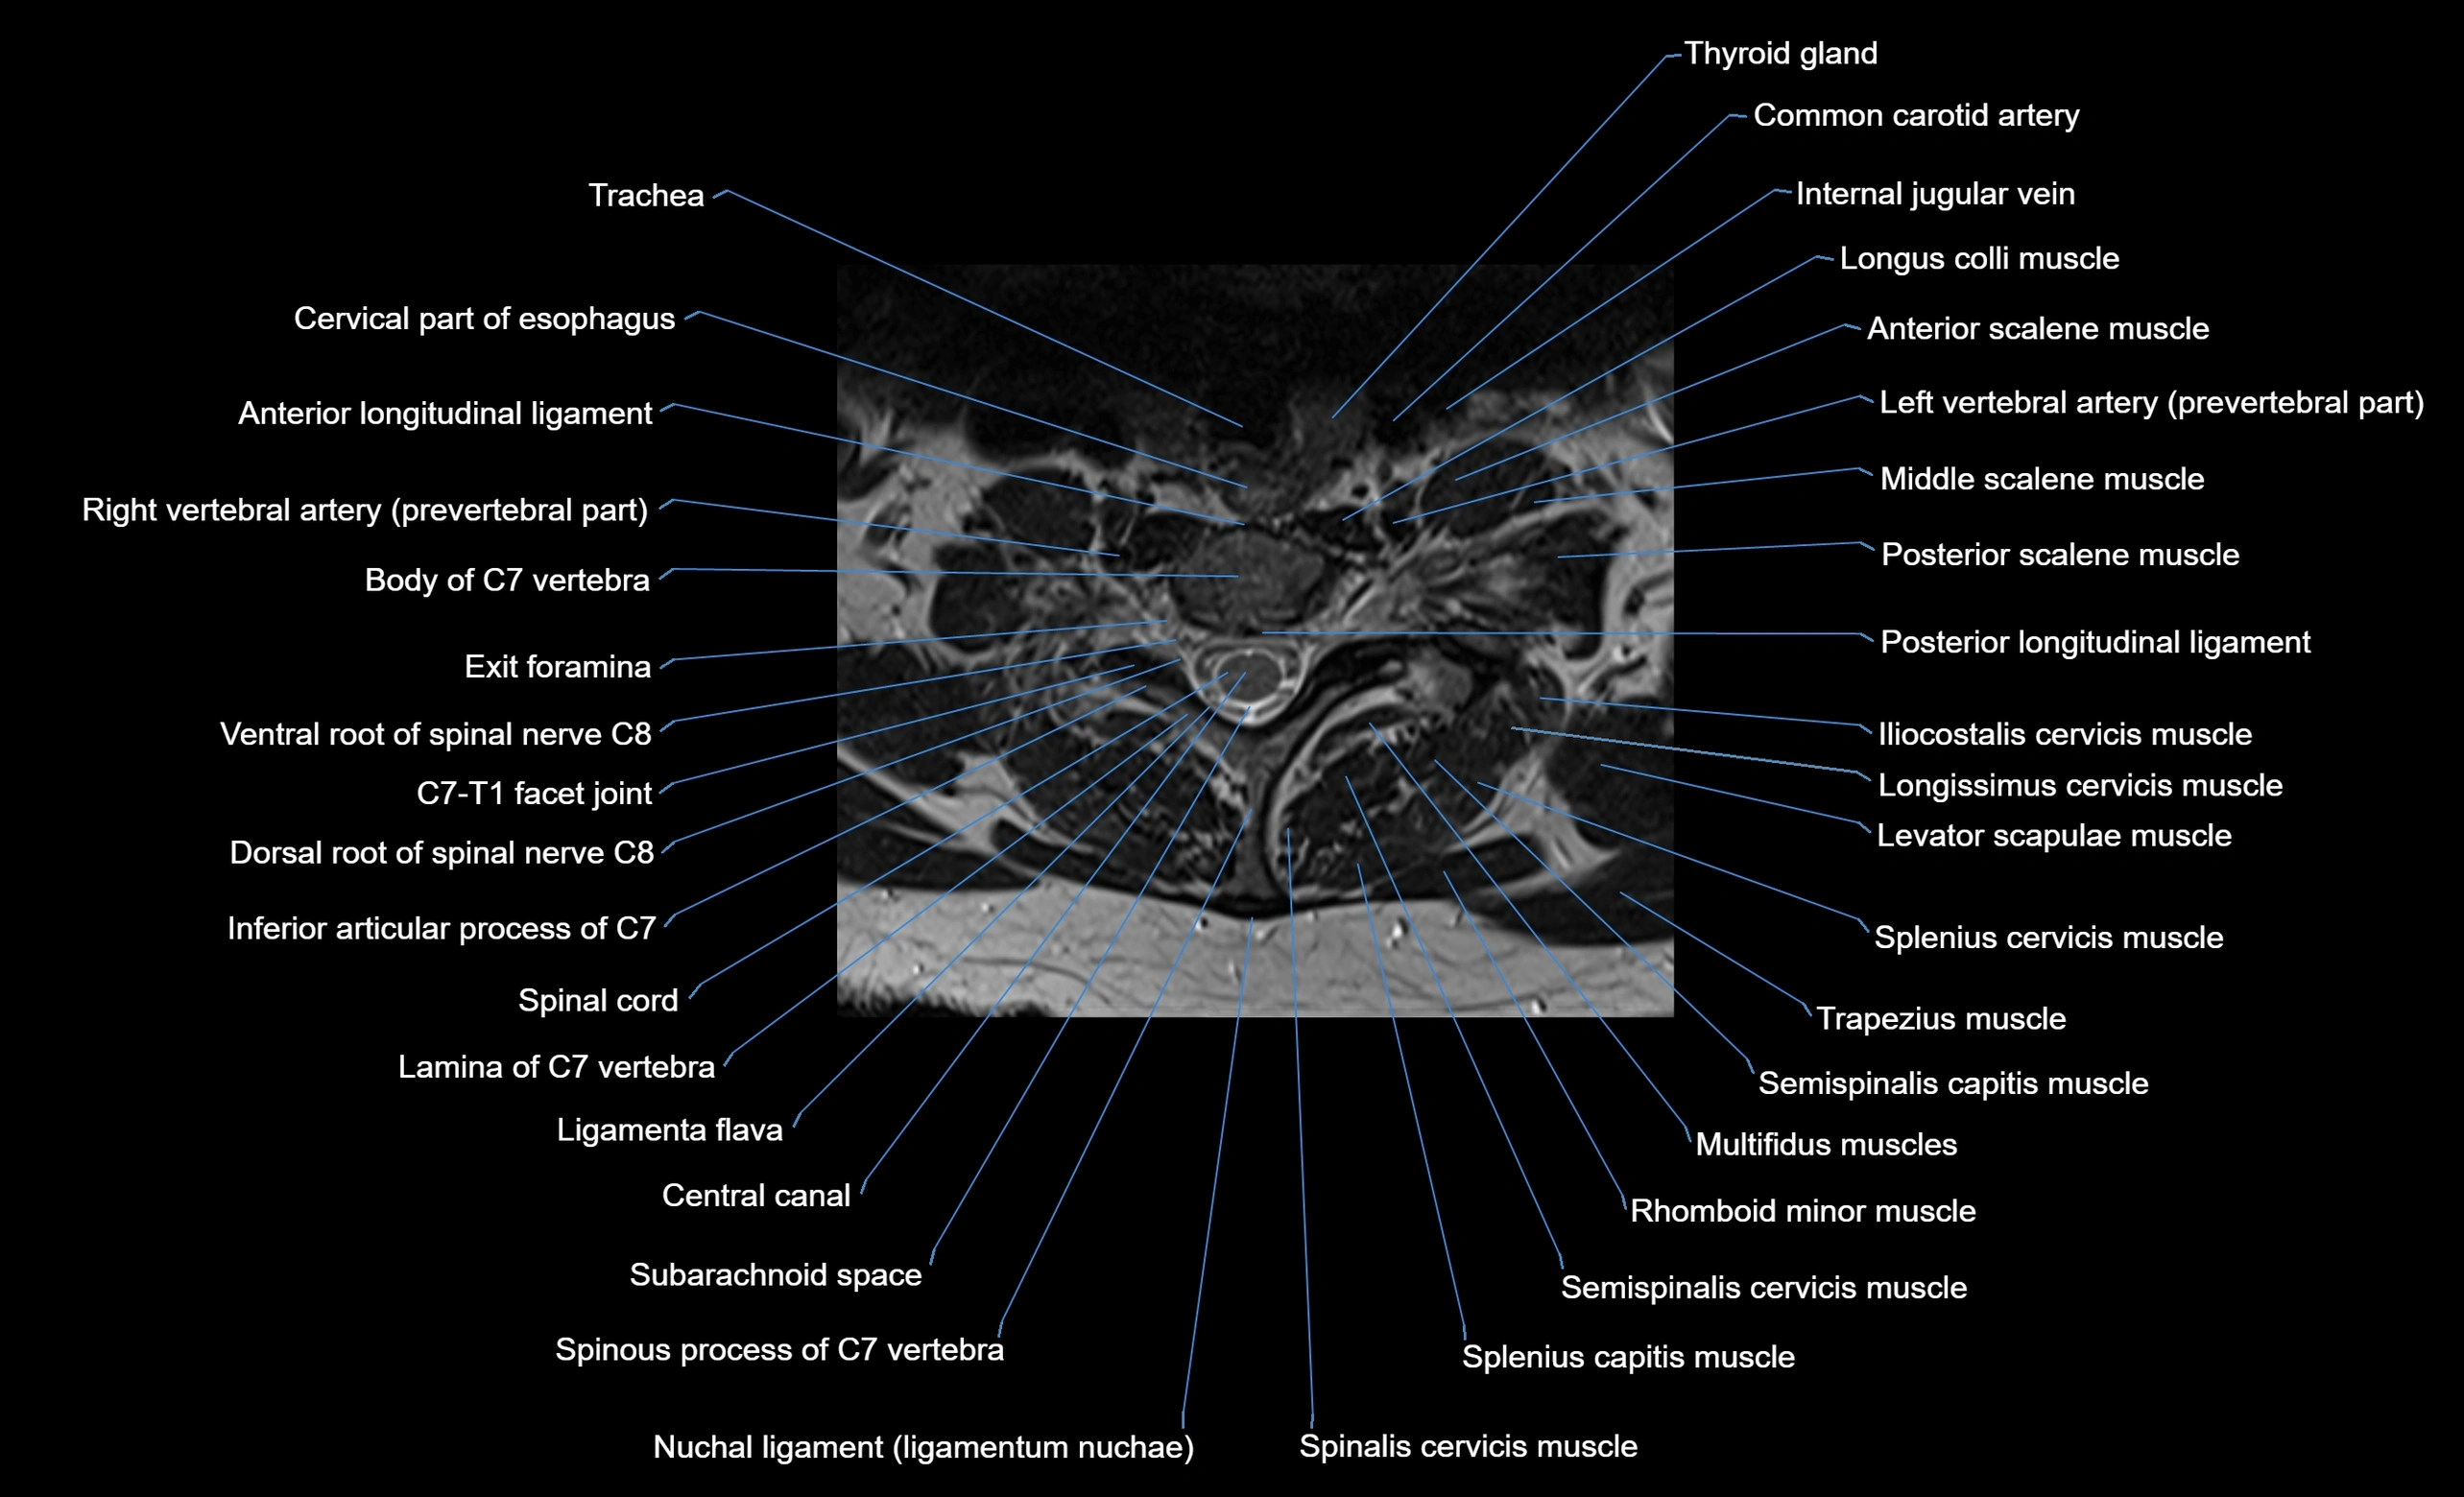

CT image

image